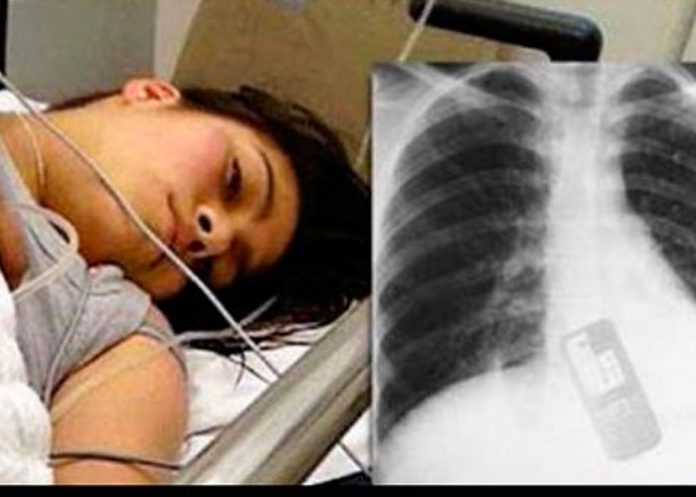

La noticia indicaba que una joven, identificada como Adriana Andrade, no encontró mejor manera de impedir que su novio leyera los mensajes de texto de su celular que tragándoselo .

Supuestamente, la mujer de 19 años se tragó el celular cuando su novio le pidió el equipo para revisarlo. Ante esto, en un acto que ha desconcertado a muchas personas en el mundo, la muchacha procedió a metérselo a la boca y tragárselo.

El portal indica que el insólito hecho ocurrió en Brasil, donde el novio, los médicos, familiares y amigos de Adriana, trataban de averiguar qué es lo que ocultaba la muchacha en los mensajes del celular para haber tomado esa tonta y peligrosa decisión.

Asimismo, hicieron creer que Andrade fue trasladada a un hospital cercano donde fue atendida antes de que lo ocurrido provocara una desgracia.

"Los médicos y el personal del hospital no dejaban de comentar la hazaña que realizó Adriana y afirmaron que están ansiosos por saber qué es lo que hay en ese teléfono celular, señalaba la broma que en pocos minutos fue compartida por miles de personas y medios de comunicación en el mundo" dice la nota.